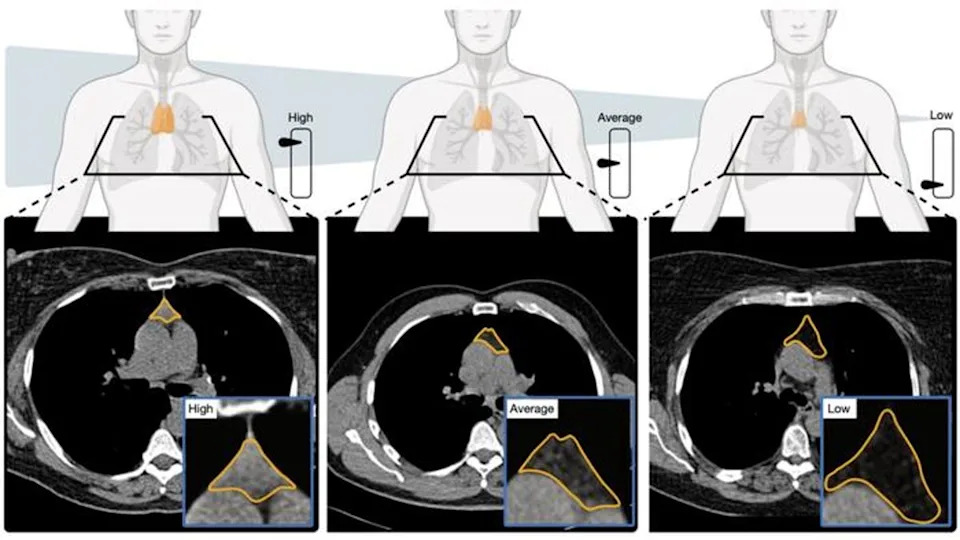

AI model analyses CT scans to estimate thymic health. Image depicts a comparison between high, average, and low thymic health and corresponding CT images (Mass General Brigham/Nature)

The thymus of each participant was evaluated by measuring its size, structure and composition, creating a “thymic health” score.